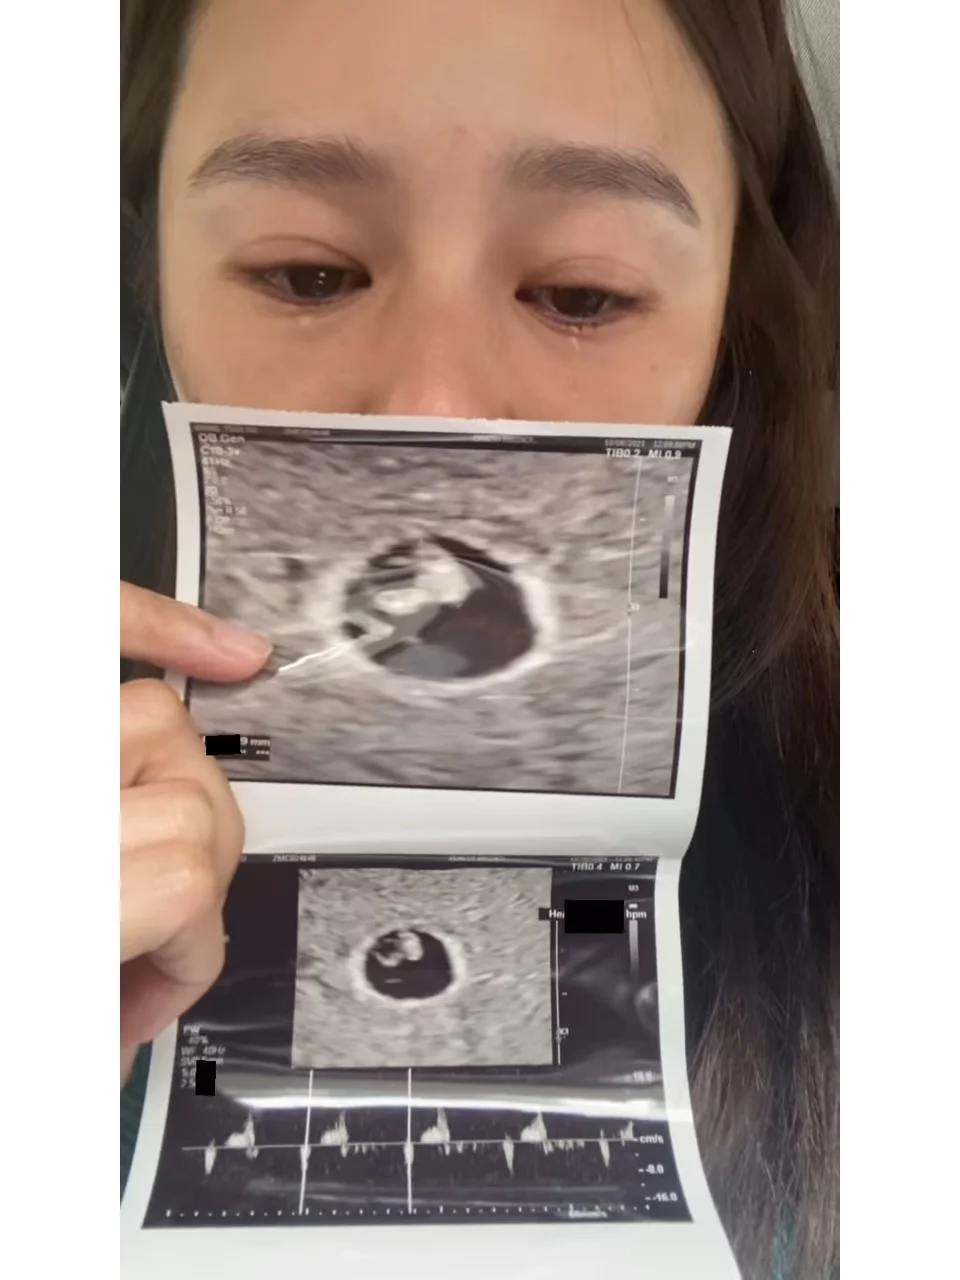

43岁黄翠如与萧正楠在2018年结婚,结婚6年终于传出喜讯,上月中在社交平台透露三年前曾经历过流产,如今成功怀孕,不少圈中好友及网民都纷纷送上祝福。

讲到工作,黄翠如称会选择适合现时状态的工作,会暂停需要飞到外地的工作。问到是否因之前小产过要特别小心?她强忍泪水说:“我发现好有趣的是,孩子真的是缘份,当他莅临的时候,我今次好感受到,当天赐给你这份礼物时,他会好坚强。”

黄翠如说这段话时三度伤感落泪,要用纸巾拭泪以及背对镜头整理情绪。对于穿着有跟鞋出席活动,黄翠如表示访问后就会换鞋,至于选择顺产还是剖腹,她表示未决定,要看医生安排。